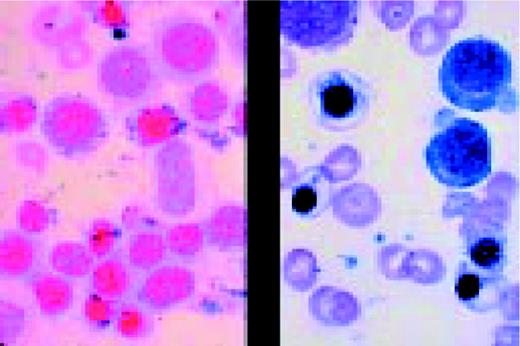

Slide E30

Myelodysplasia. (L) Marked erythroid dyspoiesis is seen in this high-dry view. Diagnosis was Refractory anemia with ring sideroblasts (RARS) (R) An iron-stain in the same patient showing perinuclear rings of iron-laden mitochondria.FIG126